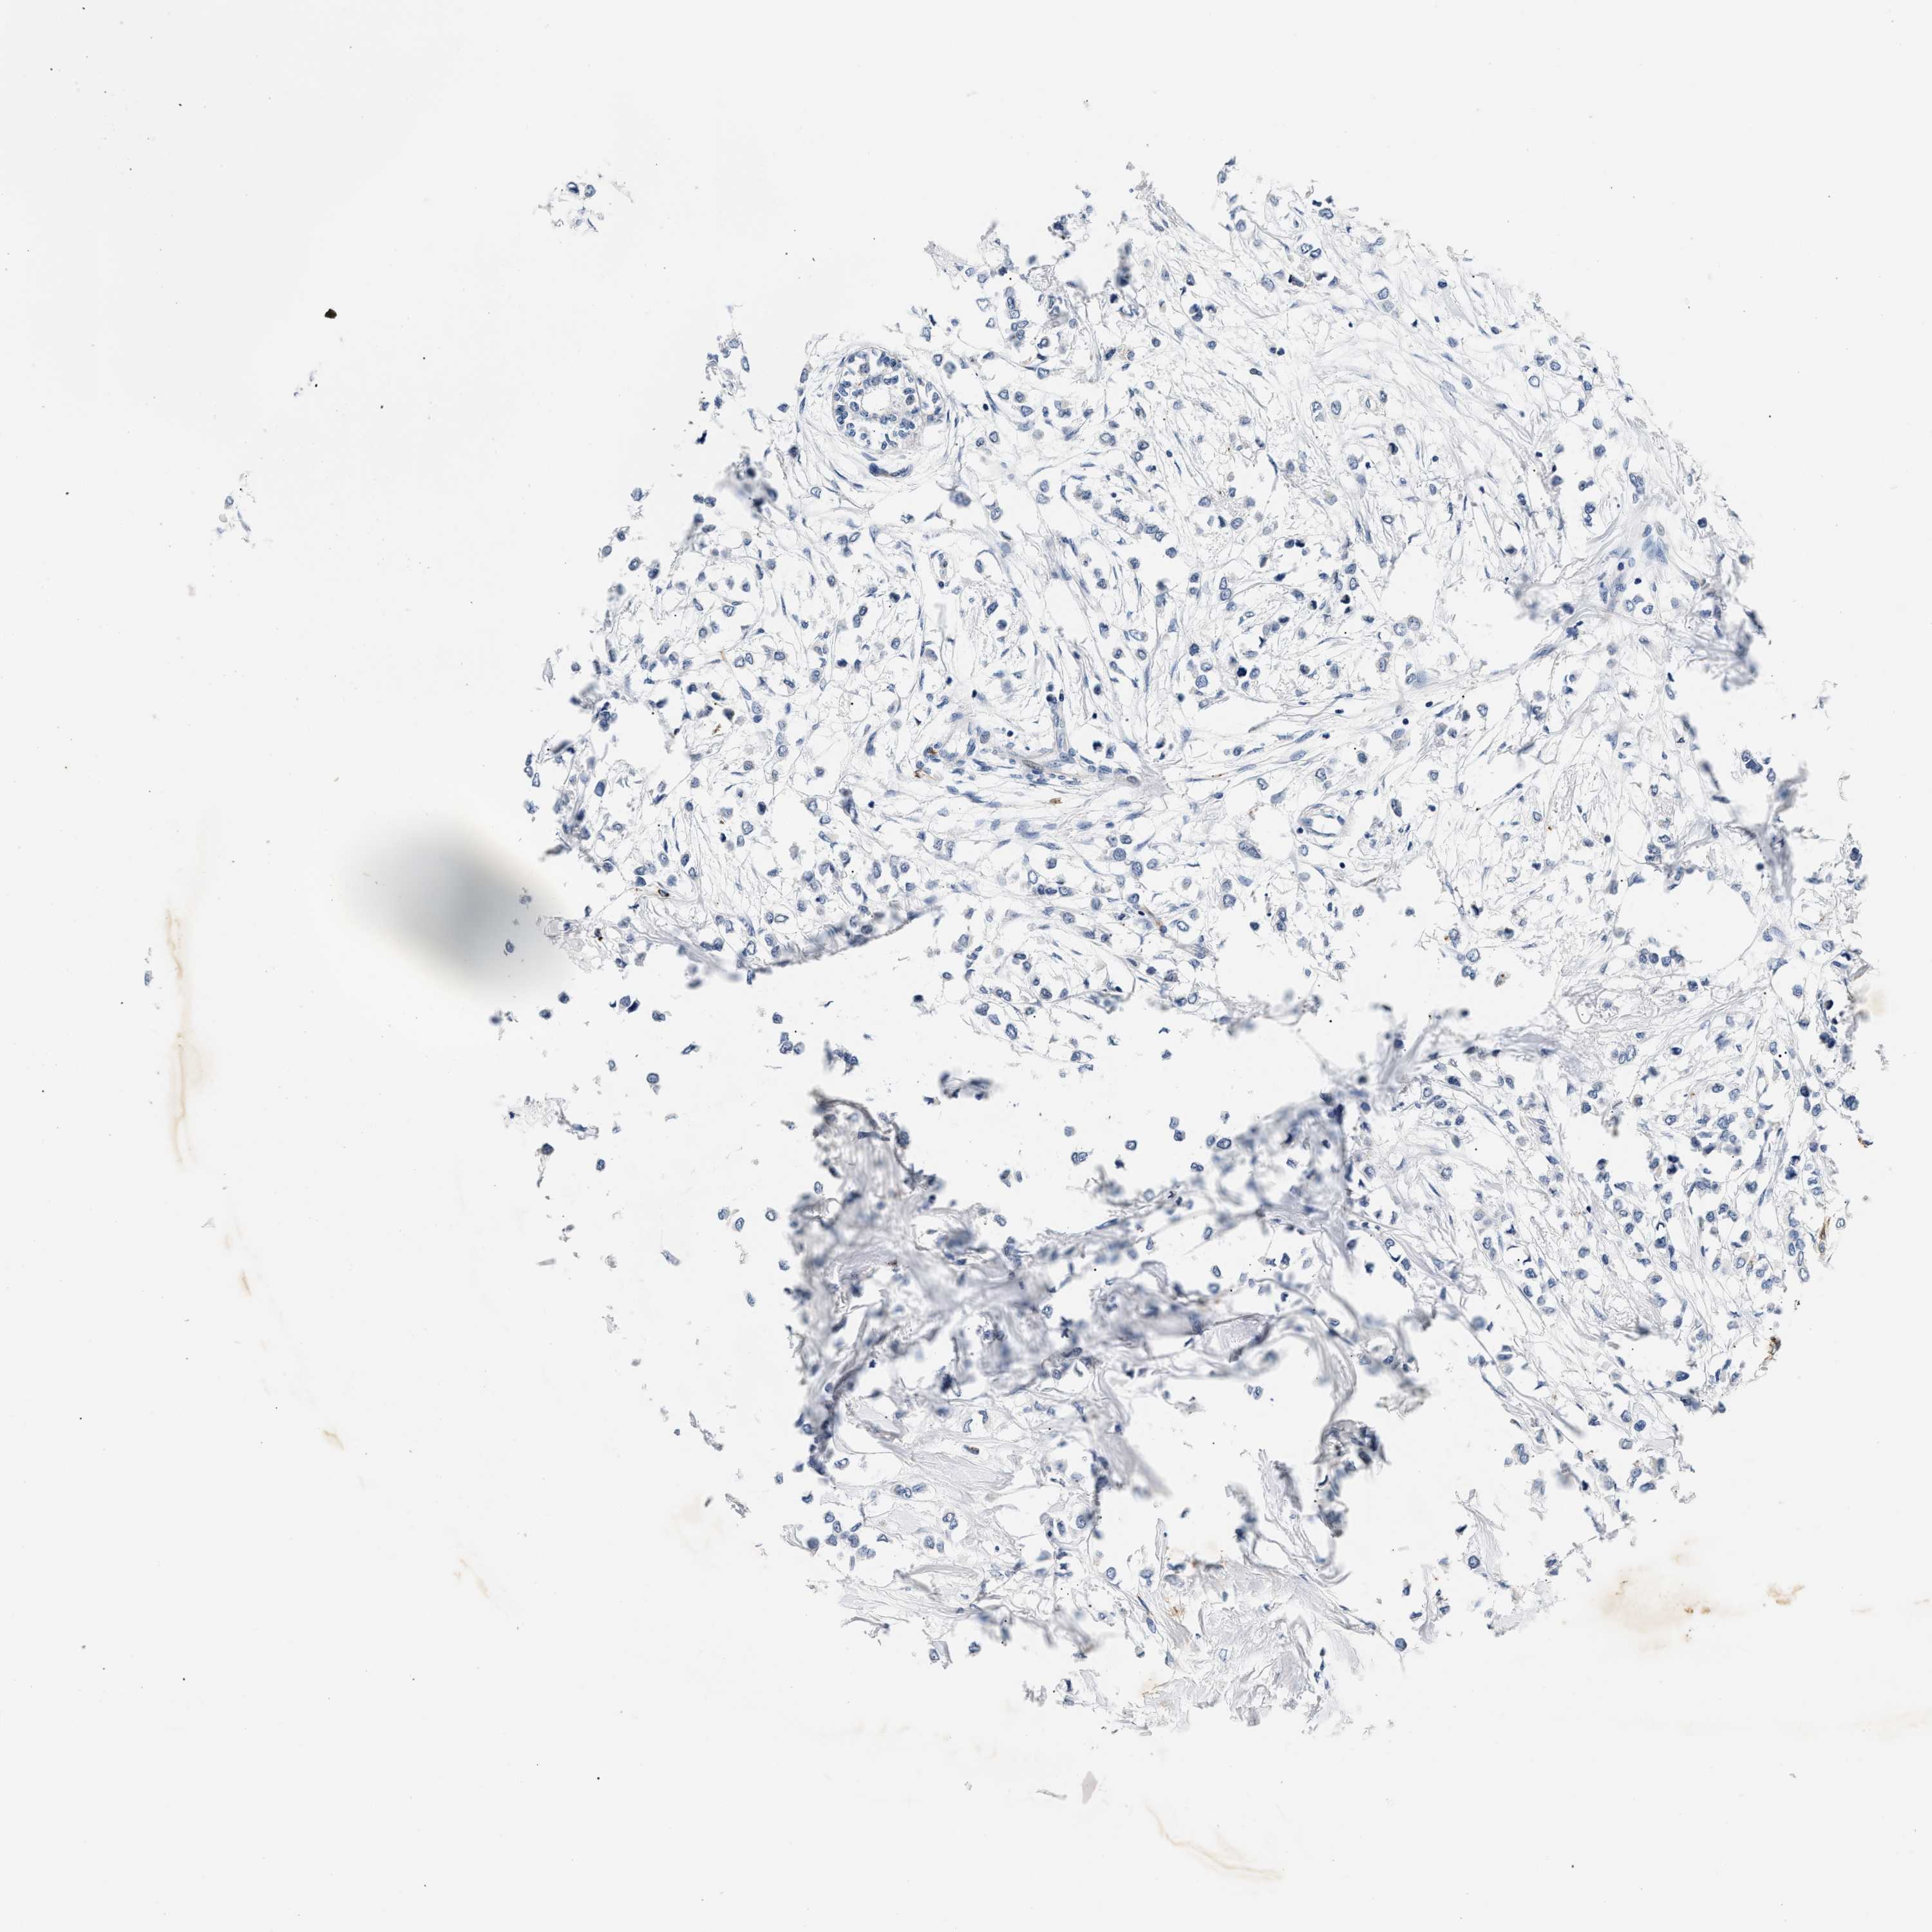

CANCER BREAST CANCER Show tissue menu

BRCA TCGA BRCA VALIDATION PROTEIN EXPRESSION